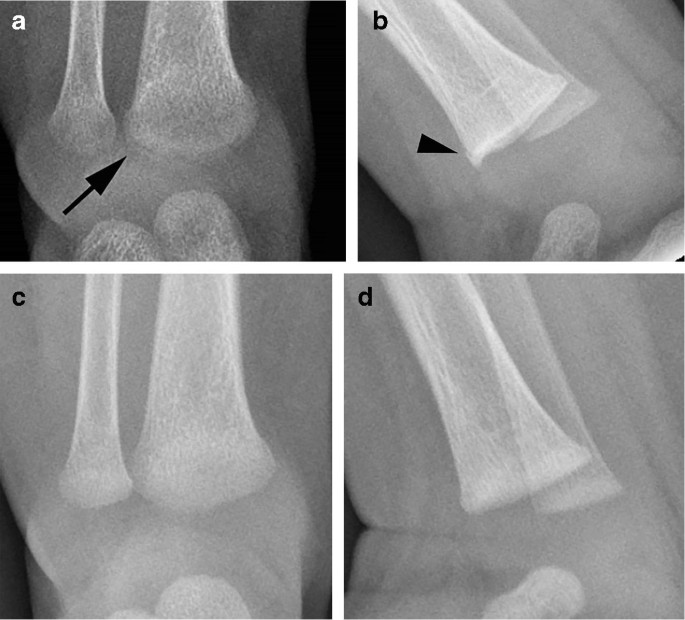

Metaphyseal fractures have not been included as they are frequently less symptomatic and it is not possible to accurately identify the date of injury . The level of interobserver agreement for the presence of the radiological features of fracture healing was also assessed . . . . Accurate dating of fractures in infants is an important but difficult . . .

Radiologic dating of fractures is an inexact science . Most radiologists date fractures on the basis of their personal clinical experience, and the literature provides little consistent data to act as a resource . There is an urgent need for research to validate the criteria used in the radiologic dating of fractures in children younger than 5 years .

It is known that it is more difficult to date certain fractures over others including metaphyseal fractures and skull fractures . Experienced paediatric radiologists are usually instructed to assist in such cases as they have the skill and up to date knowledge/ experience to date the fractures are easily as possible .

These metaphyseal abnormalities were identified from postmortem radiogra-phy and correlated with microscopy . The au-thors concluded the metaphyseal alterations represented partial or complete planar micro- fractures that transected the primary spongio-sa adjacent to the growth plate . These micro- fractures usually resembled a "bucket-handle"

Specific fractures . A number of fractures have been recognised as highly specific to non-accidental injuries (rather than accidental injury) . They include: metaphyseal fracture (so-called bucket handle fracture or corner fracture ) present in up to 39-50% of abused infants <18 months; said to be virtually pathognomonic of NAI; rib fractures